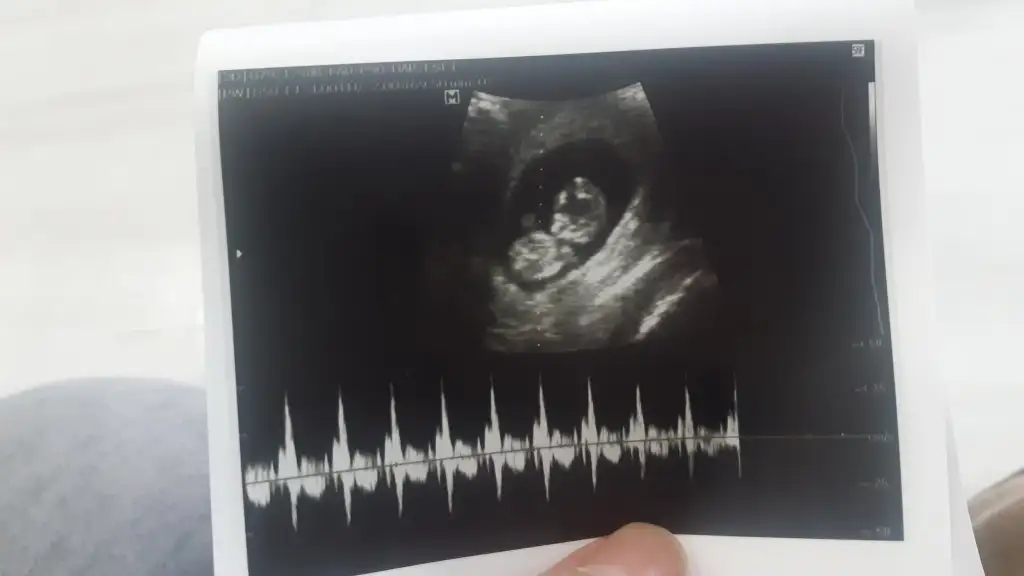

Maalesef tahmin için çok büyük canımMerhabaa bakar mısınız bizedeadet tarihine göre 11 ultrasona göre 12 haftalık karından ☺